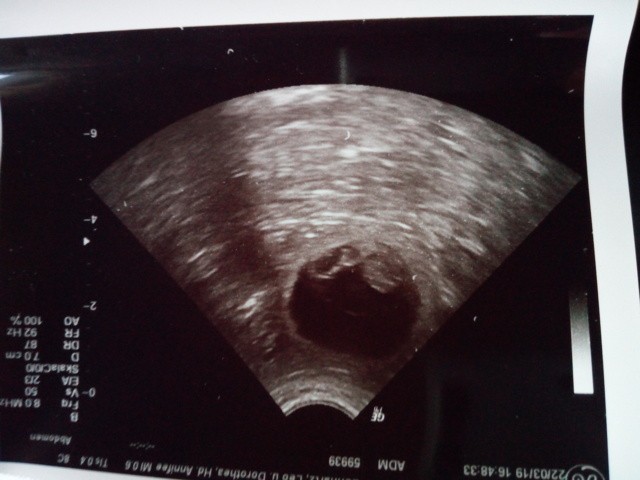

22.3.2019 Ultraschalltermin

Nun ist es amtlich ! Hurra sie ist trächtig.

Wir haben die Herzen schlagen sehen.